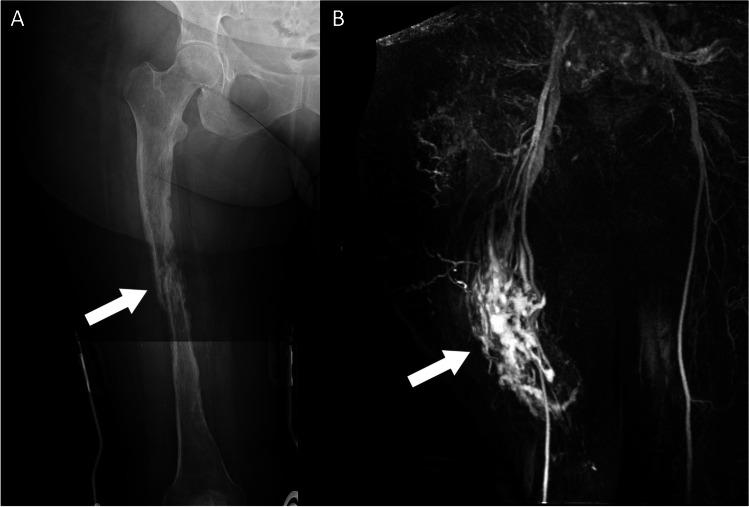

Somatic overgrowth disorders comprise a wide range of rare conditions that present with focal enlargement of one or more tissue types. The PI3K-AKT-mTOR pathway is a signalling pathway that induces angiogenesis and cell proliferation, and is one of the most commonly overactivated signalling pathways in cancer. The PI3K-AKT-mTOR pathway can be up-regulated by genetic variants that code for proteins in this pathway, or down-regulated by proteins that inhibit the pathway. Mosaic genetic variations can result in cells that proliferate excessively in specific anatomical locations. The PIK3CA-related overgrowth spectrum (PROS) disorders include CLOVES syndrome, macrodystrophia lipomatosa, and Klippel-Trenaunay syndrome among many. The neurofibromatosis type 1 (NF1) gene encodes neurofibromin which down-regulates the PI3K-AKT-mTOR pathway. Thousands of pathological variants in the NF1 gene have been described which can result in lower-than-normal levels of neurofibromin and therefore up-regulation of the PI3K-AKT-mTOR pathway promoting cellular overgrowth. Somatic overgrowth is a rare presentation in NF1 with a wide range of clinical and radiological presentations. Hypertrophy of all ectodermal and mesodermal elements has been described in NF1 including bone, muscle, fat, nerve, lymphatics, arteries and veins, and skin. The shared signalling pathway for cellular overgrowth means that these radiological appearances can overlap with other conditions in the PIK3CA-related overgrowth spectrum. The aim of this review is to describe the genetic basis for the radiological features of NF1 and in particular compare the appearances of the somatic overgrowth disorders in NF1 with other conditions in the PIK3CA-related overgrowth spectrum.